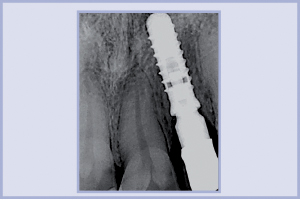

- Fig. 26 – OPT in fase chirurgica, prima dell’applicazione del tappo di guarigione

Questa paziente è giunta alla nostra osservazione per la riabilitazione protesica del 45. Il dente, precedentemente devitalizzato e ricostruito, era gravemente compromesso da una carie secondaria della corona e da una frattura del terzo prossimale della radice nel cui canale beava una vite endocanalare (fig. 25). La situazione imponeva, quindi, una riabilitazione implantare che avesse consentito un’ottima prognosi a lungo termine. Si è quindi proceduto ad applicare un impianto post-estrattivo immediato. Effettuato un lembo a spessore parziale, con incisioni paramarginali ai denti adiacenti e senza rilasci verticali, dopo un’attenta estrazione del residuo radicolare ed un courettage dell’alveolo post-estrattivo, si è preparato il sito implantare con frese Leone e Sonosurgery® (Komet). Abbiamo, quindi, posizionato un impianto di diametro 4,8, lunghezza 12 mm e, di seguito, un tappo di guarigione da 5 mm di tragitto transmucoso (fig. 26). Dopo un periodo di osteointegrazione di tre mesi, il caso è stato completato con una corona in zirconia-ceramica (figg. 27-32).